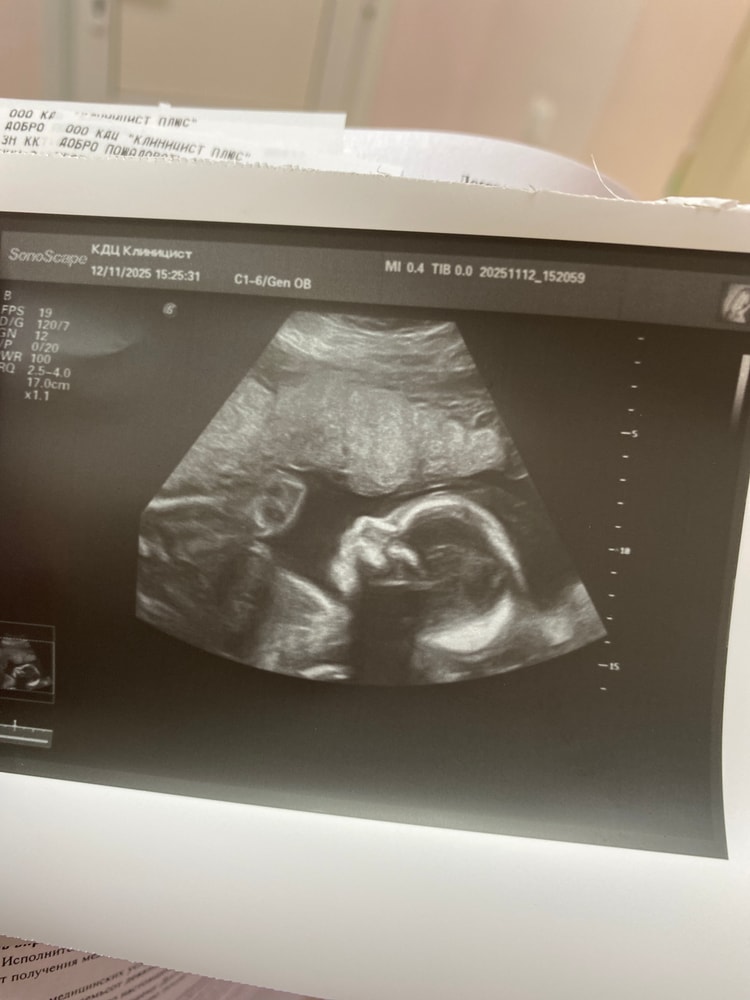

Девочки, скажите пожалуйста было ли у кого то так, что всю беременность малыш по узи лежал головкой вниз?Т.е не менял положение ни когда.

Здравствуйте. Беременность акушерская неделя 27 недель где-то. Бедренная кость соответствует как раз неделям, а вот голова,её окружность и окружность живота ушли на 13 дней вперед,то есть 28 недель 6 дней.Неясно почему. Страшно ли это? Или нормально?